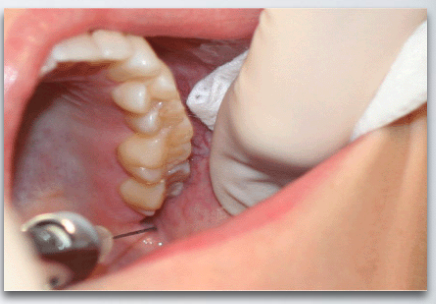

what is the proper injection site for long buccal nerve block?

buccal side of 2nd or 3rd molar (injection depth is very shallow)

what is the proper insertion point for long buccal nerve block?

Just medial to the external oblique ridge at the level of the occlusal plane

what is the proper insertion path for long buccal nerve block?

Through the mucosa and buccinator muscle until bone in gently contacted on the anterior ramus

what is the proper insertion depth for long buccal nerve block?

2 – 3 mm (very superficial)